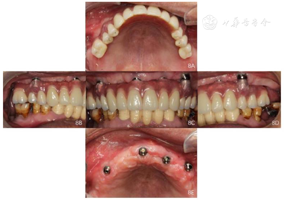

口外检查:颌面部大致对称,面下1/3前突,双侧颞下颌关节未见异常(图1)。

面照;F:正面照口内检查:15、16、24、25、26、27缺失,缺牙区牙槽嵴低、窄;14、12、11、21、22Ⅲ度松动、17Ⅱ度松动、18Ⅰ度松动,牙龈退缩,部分牙根暴露,前牙呈扇形分开,高笑线。31、32、41、42缺失,已行31、32、33、41、43烤瓷固定桥义齿修复(5单位);36缺失,37近中倾斜,近中邻面及远中邻

面可见黑色龋坏组织,质软,探诊、冷诊不适,叩诊(一);47缺失,缺牙区牙槽嵴低平,46牙龈退缩,根分叉暴露,

面可见白色充填物,完整。未见龈上结石,全口牙牙龈退缩,部分牙根外露。前牙重度深覆

重度深覆盖,双侧后牙无稳定咬合关系(图1)。

(1)种植一期手术:①阿替卡因肾上腺素注射液局麻下拔除上颌余留牙。②沿16-26区域牙槽嵴顶全层翻瓣,清除拔牙窝内炎性肉芽组织,平整牙槽嵴顶。③分别于12、22、25区定点,逐级备洞,12、22植入Nobel Speedy 4.0 mm×13 mm种植体;25近中倾斜植入Nobel Speedy 4.0 mm×15 mm种植体;④超声骨刀于13、14、15牙槽嵴顶8 mm处行唇、颊侧骨壁近远中向开窗,开窗面积约15 mm×8 mm,剥离上颌窦底黏膜后,15区定点,推开上颌窦底黏膜,近中倾斜备洞直达鼻底,倾斜植入Nobel speedy 4.0×18 mm种植体。⑤4颗种植体初期稳定性均达到35NCm,15颊侧骨开窗区种植体表面覆盖浓缩生长因子(Concentrated growth factor, CGF)(视频4)。⑥拔除18,12旋入RP17°3 mm复合基台,22旋入RP17°4 mm复合基台,15、25分别旋入RP 30°5 mm复合基台,修整牙龈组织,黏膜瓣复位、缝合创口,拍摄曲面体层片(图3)。

(2)即刻修复:制取上下颌硅橡胶印模,利用术前可摘局部义齿转移颌位关系,制作丙烯酸树脂临时固定义齿,咬合关系恢复至第二前磨牙,调整咬合。口内固定修复螺丝加力至15N.CM,牙龈硅橡胶封闭螺丝孔,拍摄曲面体层片(图4,图5)。